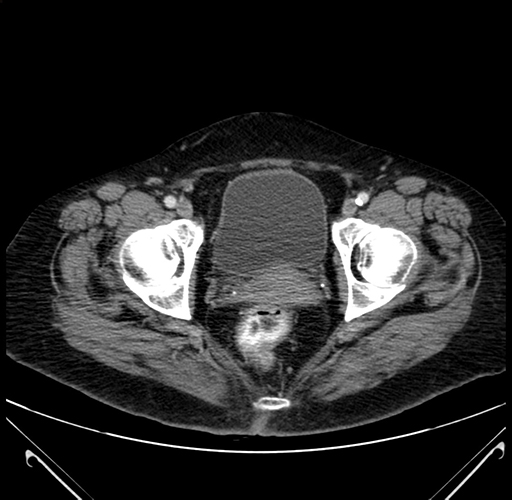

Pre-Chemo: Axial Venous